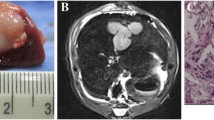

The Combination of HGFK1 and TAE Prolonged the Survival Time

To evaluate the anti-tumor effect of PH1/HGFK1 in vivo, we first established the rabbit HC orthotopic transplantation model with a success rate of 85.7% (36/42). As shown in Fig. 3A, the survival rate dropped to 0 in the control group on day 27, which was prolonged to 36 days in the TAE group. Furthermore, the survival time has increased to 42 days in the PH1/HGKF1 group and 43 days in the PH1/HGKF1 + TAE group (P > 0.05). When compared with the PH1/HGKF1 + TAE group, the mean survival time was significantly shorter in the control group and the TAE group (P < 0.05).

The Combination of HGFK1 and TAE Inhibited Tumor Growth In Vivo

The tumor size on days 7 and 14 was all significantly smaller in PH1/HGKF1 + TAE group compared with the control group (P < 0.05). There was no significant difference in the tumor size between the PH1/HGKF1 and TAE groups (P > 0.05). Meanwhile, the tumor size was the smallest on day 14 in the PH1/HGKF1 group (Fig. 3B). After modeling, the tumor area showed a low signal on T1WI and a high signal on T2WI with a more obvious signal in the center of some tumors in all HC orthotropic transplantation rabbits. Moreover, DCE perfusion enhancement showed that there was no blood supply in the center of the tumor. There was no statistically significant difference in lesion size between the four groups before treatment. Seven days after treatment, the tumor enhancement area was significantly reduced in both PH1/HGKF1 + TAE group and the TAE group (Supplementary Fig. 1).

Previous studies have determined that the microvascular contrast agent transfer constant (Ktrans) plays an important role in tumor prognosis [16]. As shown in Table 1 and Supplementary Fig. 2, the Ktrans values on days 7 and 14 were dramatically decreased in the three treatment groups in comparison with the control group (P < 0.05). However, the lowest Ktrans level was found in the PH1/HGKF1 + TAE group (P < 0.05). Moreover, the Ktrans value in the TAE group on day 14 was twice than that in the PH1/HGKF1 + TAE group (P < 0.05).